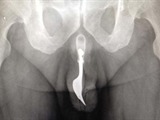

Hombre se entierra un tenedor en su amiguillo

Un australiano de 70 años vivió una insólita y dolorosa experiencia, cuando por curiosidad incrustó el utensilio de 10 centímetros en su miembro viril.

El utensilio se "perdió" dentro del miembro viril del hombre, los médicos lograron ubicarlo con el tacto y gracias a una elaborada maniobra, que involucró mucho lubricante y pinzas, lograron sacar el tenedor de su pene.